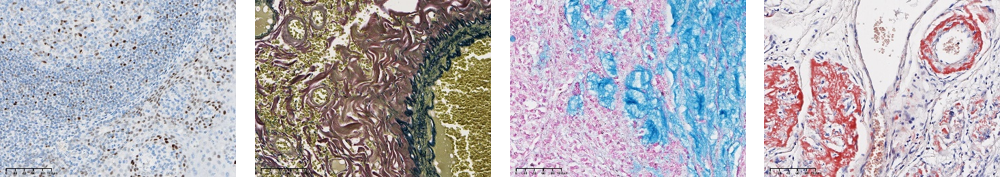

C-MYC | 彈力纖維染色 | 粘液染色 | 剛果紅染色 |